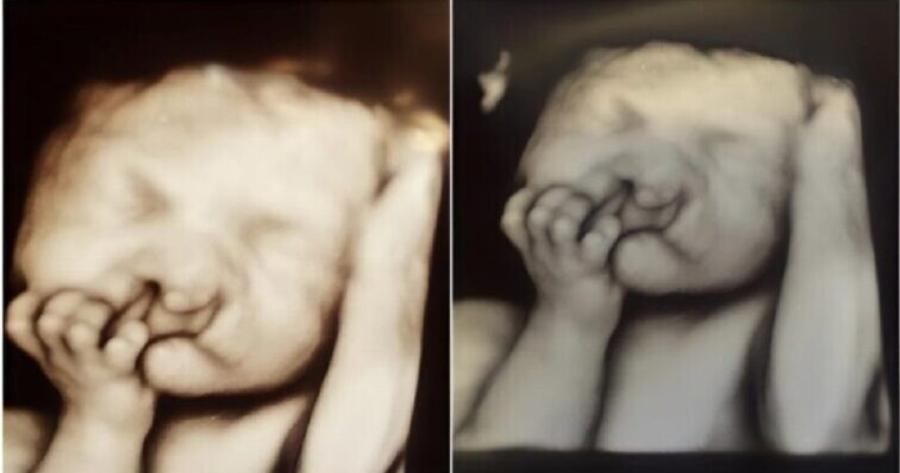

Έπαθαν σοκ όταν είδαν τις πρώτες εικόνες υπερήχων του παιδιού… Το μωρό γεννήθηκε με μια χαρακτηριστική μύτη και χείλη. Δείτε πώς μοιάζει τώρα.

Όταν η Σάρα κι εγώ είδαμε για πρώτη φορά το μωρό μας στον υπέρηχο, ποτέ δεν φαντάστηκα πόσο πολύ θα άλλαζε αυτή η στιγμή τη ζωή μας. Το μικροσκοπικό του πρόσωπο εμφανίστηκε στην οθόνη και το κοιτούσαμε με δέος 😳. Η τεχνικός έκανε ζουμ, δίστασε και ύστερα είπε απαλά ότι υπήρχε κάτι ασυνήθιστο στη μύτη και στο χείλος του. Η καρδιά μου βυθίστηκε, αλλά δεν μπορούσα να τραβήξω το βλέμμα μου. Κάθε κίνηση στην οθόνη μας γέμιζε ταυτόχρονα με χαρά και αβεβαιότητα 💔.